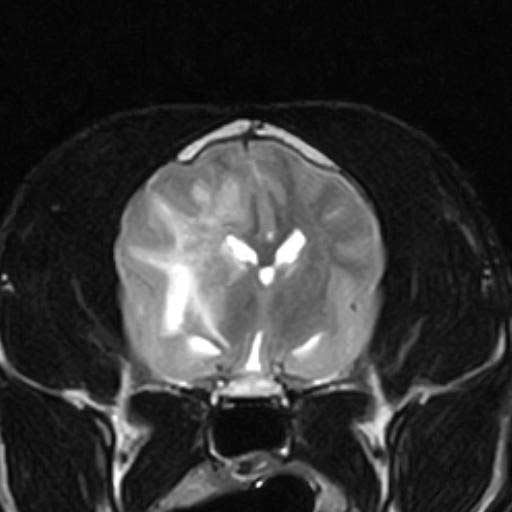

A patient’s signs cannot be used alone to diagnose MUO. Similar signs can also be caused by other neurological conditions such as cancer of the brain or bleeding into the brain. Even the most severe form of meningitis or encephalitis may not be detected by blood tests. You will always need to conduct additional tests and may recommend special imaging studies such as MRI scans in order to diagnose the problem. When done safely, cerebrospinal fluid analysis (collection of fluid around the brain) is one of the most useful tests. By doing so, it can be determined whether inflammation is present, what type of inflammation it is, and, perhaps more importantly, whether or not there is an infection present. It is rare for cerebrospinal fluid to be normal if an animal has MUO.